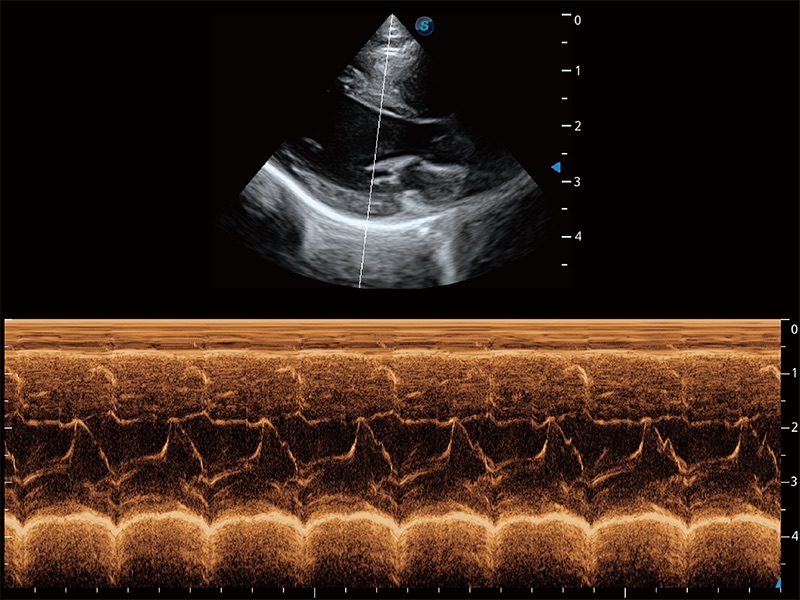

(犬)四腔心MQA

(猫)二尖瓣M型